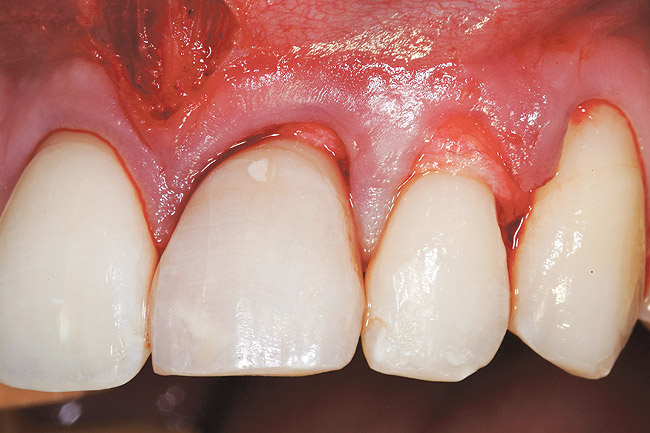

The 2.5-week postoperative clinical view can be seen in Figure 10 through Figure 12. Note the rapid soft tissue healing and maturation. At 6-weeks postoperative, tissue plasty was accomplished to blend the thickened keratinized tissue, in addition to placement of class V composite restorations at teeth Nos. 5, 6, and 11 to create a new restorative margin on the root surfaces.

Figure 10  Case One The 2.5-week postoperative view, maxillary anterior.

Figure 10

Figure 11  Case One The 2.5-week postoperative view, maxillary right.

Figure 11

Figure 12  Case One The 2.5-week postoperative view, maxillary left.

Figure 12